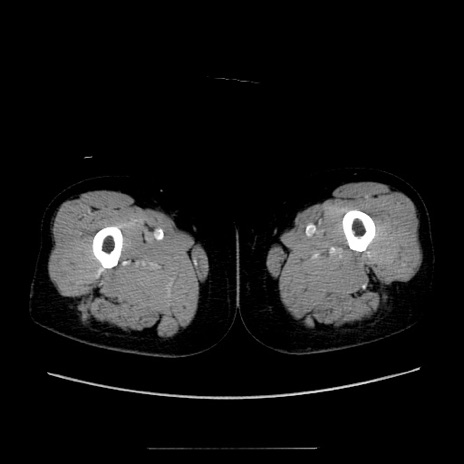

【症例】70歳代女性

【主訴】お腹が張る

【現病歴】1週間くらい前から腹部膨満の自覚あり。昨日夜から増悪したため、本日救急外来受診。

【身体所見】意識清明、BT 36.5℃、BP 165/106mmHg、HR 80bpm、SpO2 98%、腹部:膨満、軟、自発痛・圧痛なし、触診にて不快感あり、腸蠕動音:減弱

【データ】WBC 12600、CRP 1.04